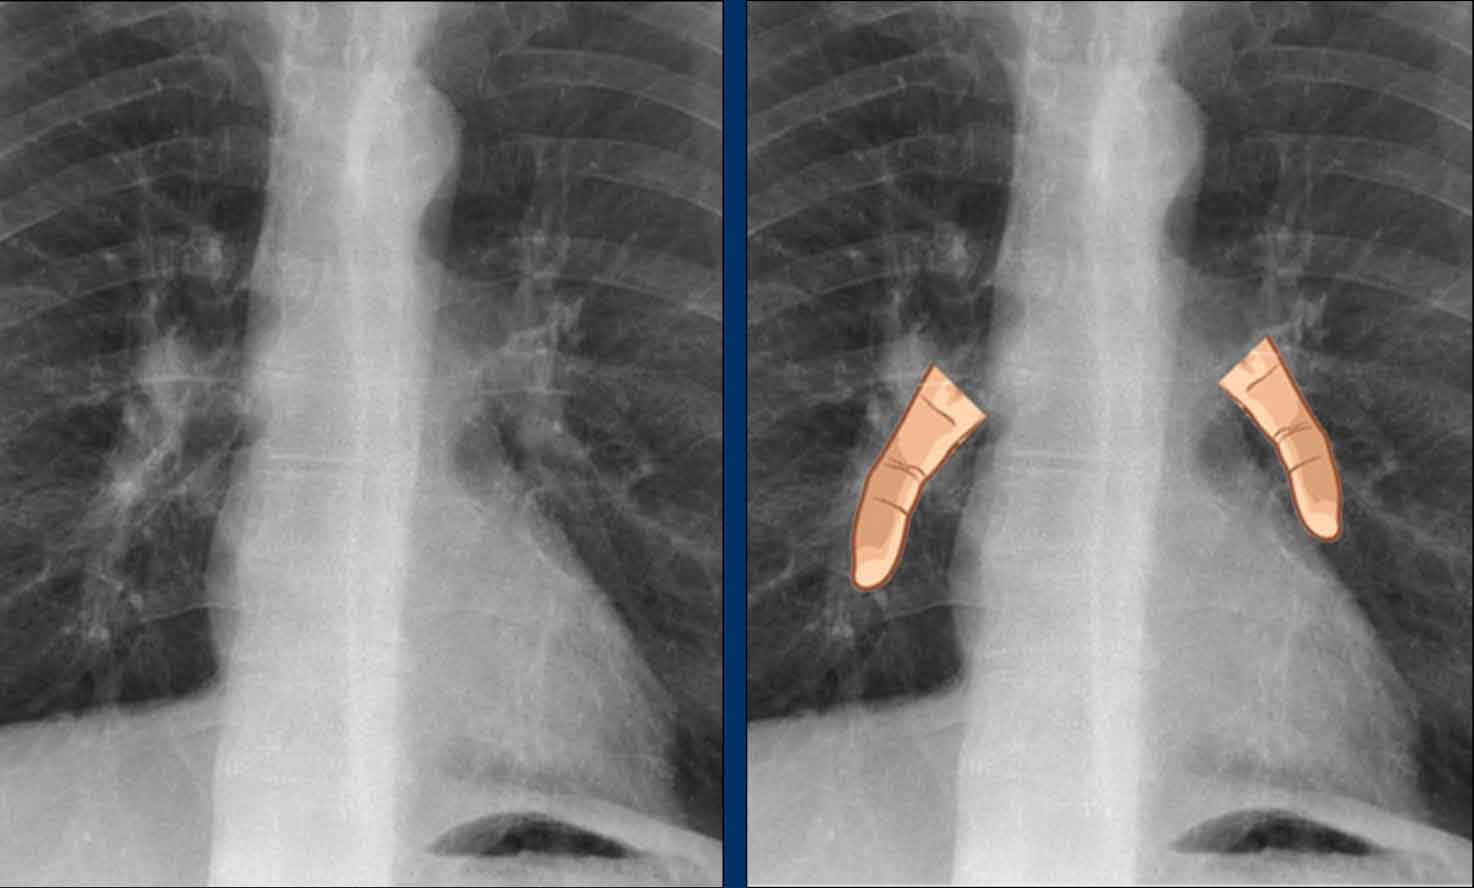

Vena azygos lobe

A common normal variant, the azygos lobe, is formed when the azygos vein takes an anomalous lateral course, creating a deep pleural fissure in the upper lobe of the right lung.

On radiographs, it appears as a thin curvilinear line traversing the right upper lung field, frequently ending in a teardrop-shaped density (the azygos vein) within the azygos fissure.

Here another patient with an azygos lobe.

The azygos vein is seen as a thick structure within the azygos fissure.

Another anatomical variant involves an accessory articulation at the anterior first rib (arrow).

At the junction of the bony and calcified cartilaginous segments, a pseudoarticulation may simulate a pulmonary nodule or mass on frontal imaging.